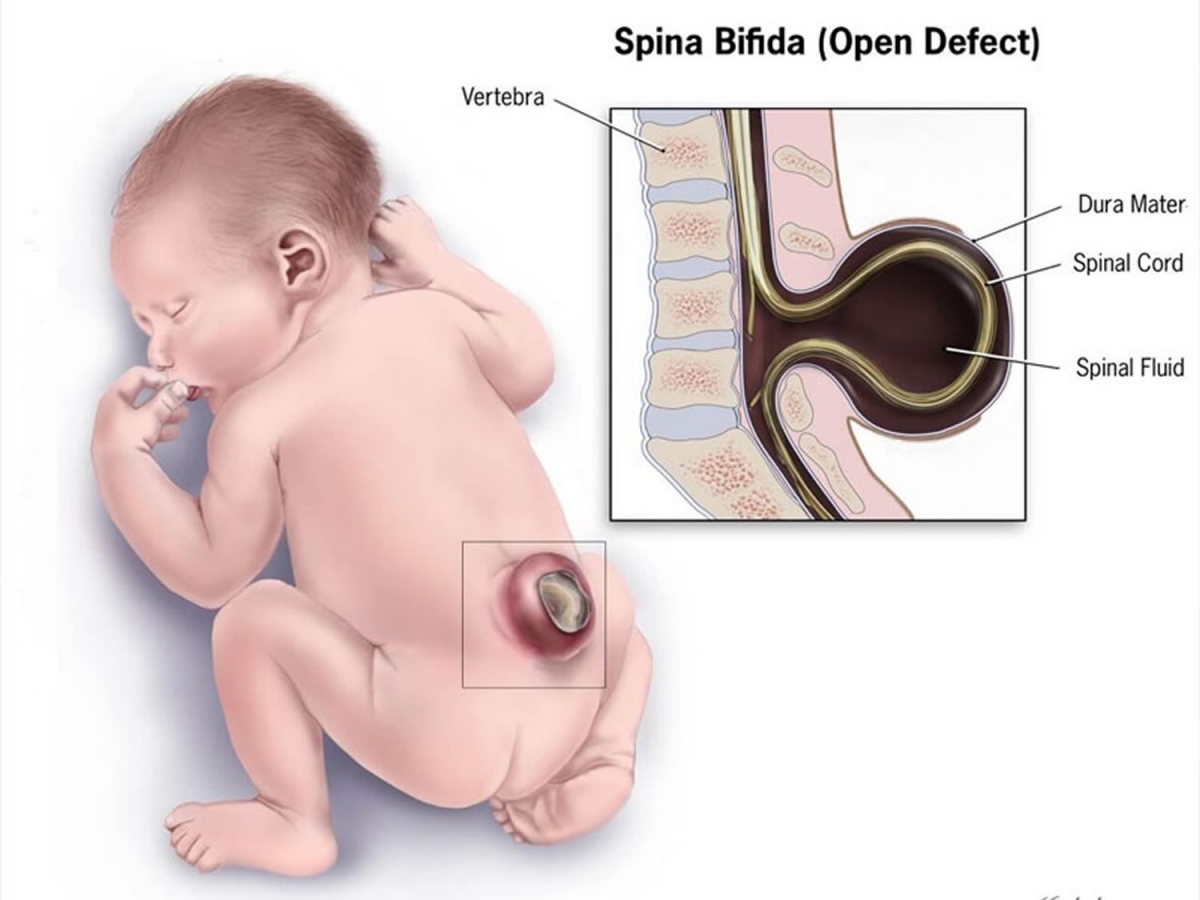

अशा प्रकारच्या शस्त्रक्रियेला त्याच प्रकारचं मोठं कारणही लागतं. या केस मध्ये बेथनच्या बाळाच्या शरीरात ‘स्पिना बिफिडा’ नावाचा दोष होता. पाठीच्या कण्याची पूर्ण वाढ न झाल्याने हा दोष उद्भवतो. खालील फोटो मध्ये याचं उदाहरण तुम्ही पाहू शकता.